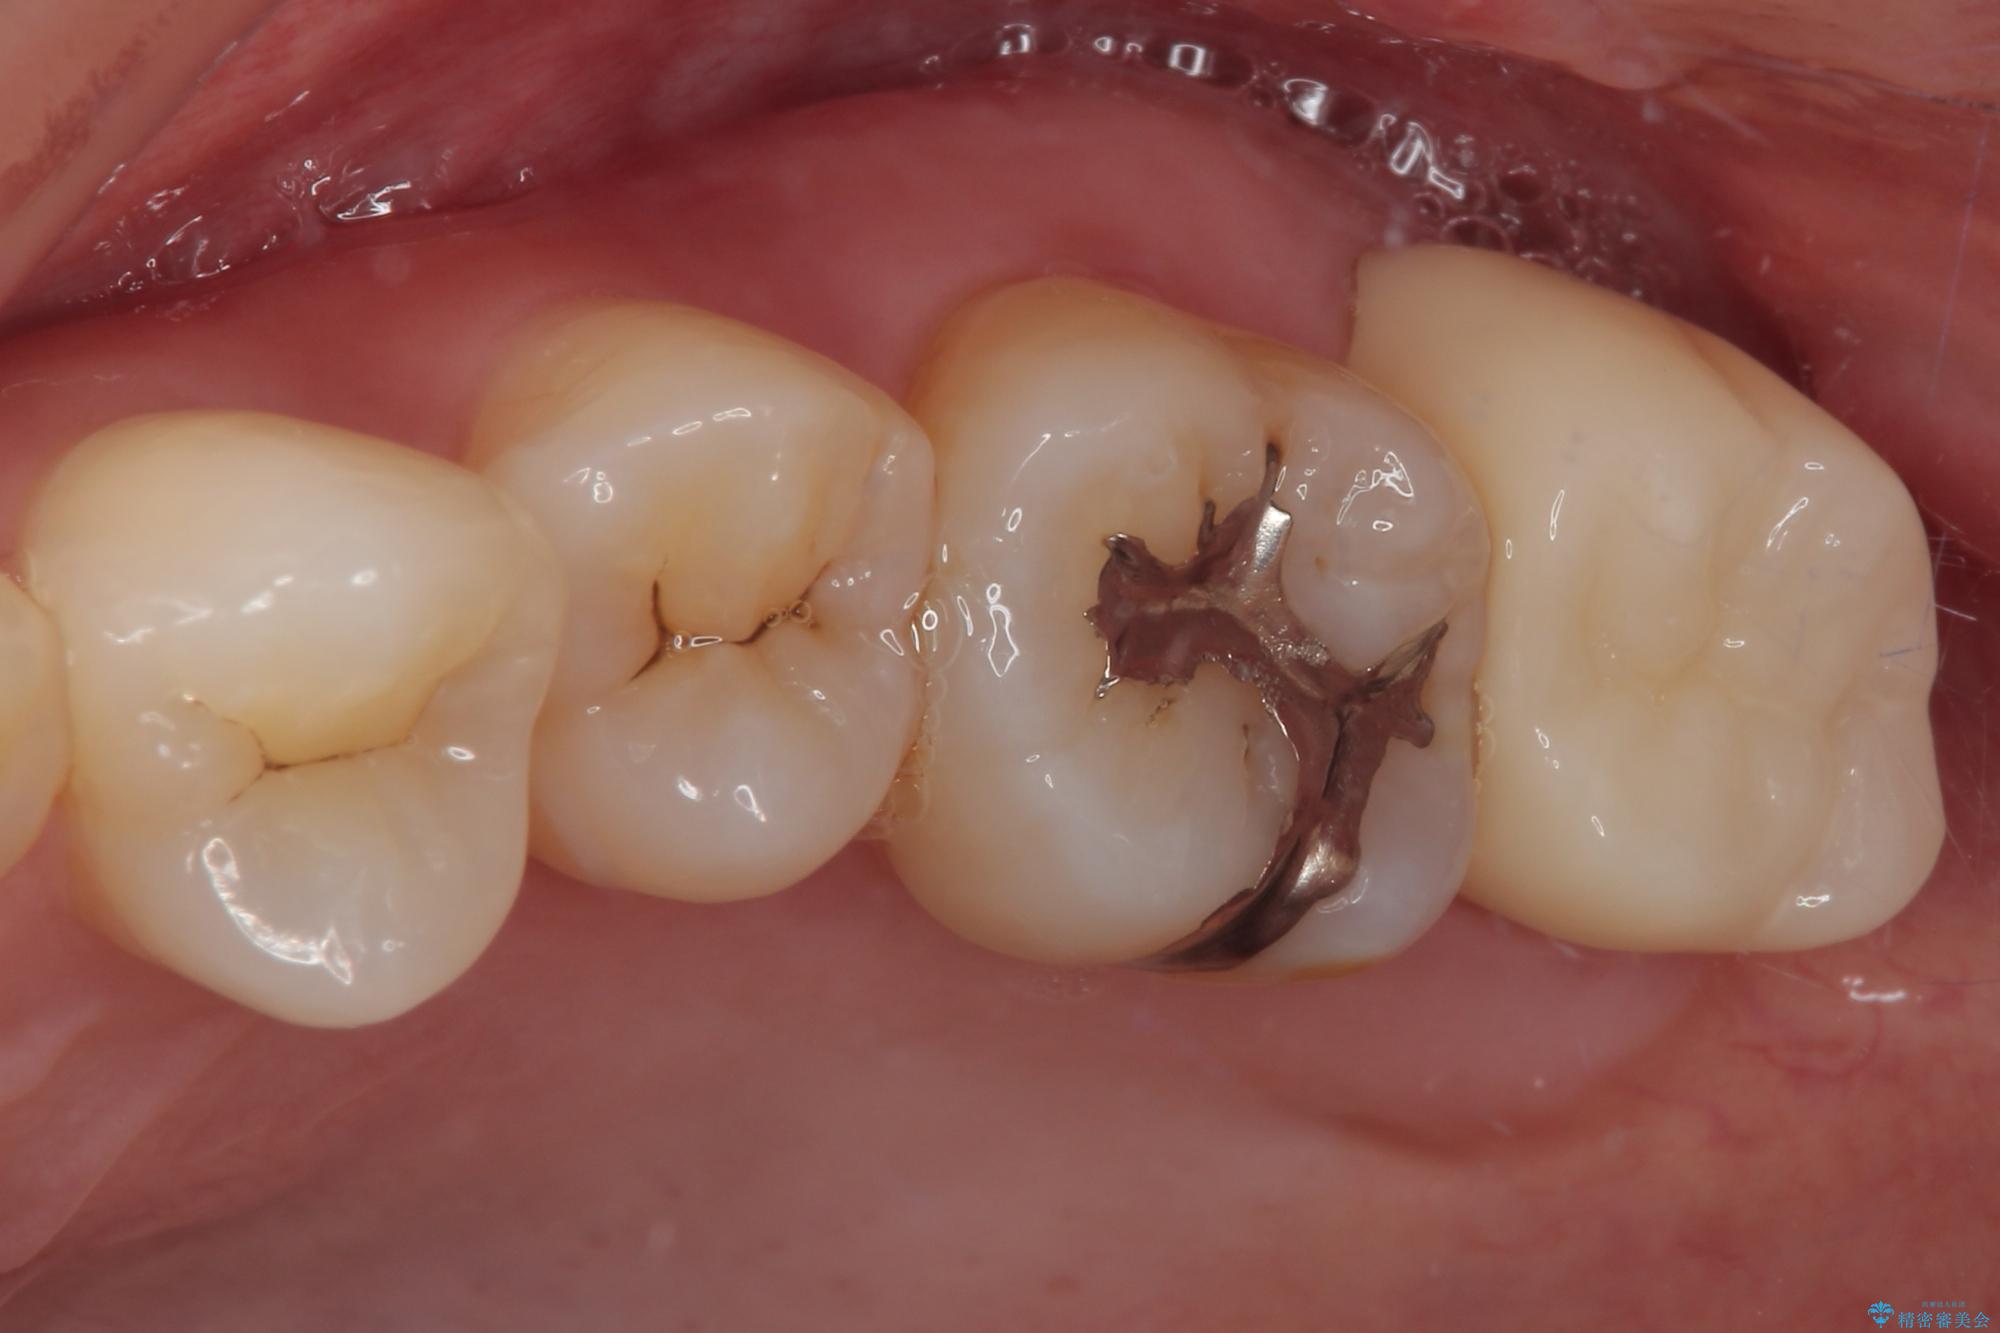

- 元々むし歯があったものの、処置が困難とのことでしたが、矯正治療を終えたので処置をしたいとのことで来院された患者様です。

左右ともに最後臼歯が頬側に顕著に突出しており、むし歯になってしまったことが想像されました。

矯正治療により処置が可能な位置に歯が移動したため、オールセラミッククラウンにて補綴治療を行うこととしました。

歯列が移動したとはいえ、左右ともに後方傾斜しており、むし歯の除去、形成(形を整える)、型取りの全てが非常に困難な処置となりました。